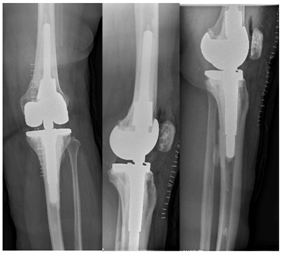

A 52-year-old woman underwent a left total knee arthroplasty 7-years prior with a cemented CR Zimmer® NexGen® total knee system (Zimmer-Biomet, Warsaw, IN) secondary to rheumatoid arthritis. She had a history of rheumatoid arthritis, lymphoma, COPD, deep vein thrombosis as well as obesity (5’5”, 226Lbs, BMI 37). She presented for follow up 5-years after her original surgery with symptoms of pain, difficulty ambulating, and an audible clunk. She demonstrated abnormal AP mechanics with significant anterior tibia translation. She was noted to have near complete wear through the posterior medial corner of her polyethylene (Figure 1) and was subsequently revised to 14mm AC polyethylene with resolution of her abnormal mechanics (Figure 2).

Figure 1 AP/Lateral left knee 5years from TKA with medial joint space narrowing and anterior translation of the tibia.

Figure 2 AP/Lateral left knee, status post revision TKA to a 14mm AC constrained polyethylene with resolution of joint space asymmetry and appropriate alignment on the lateral view.